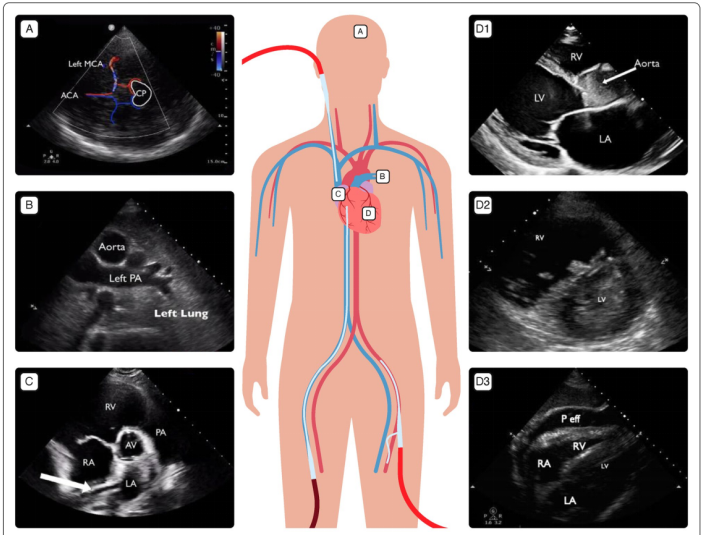

2. ECMO置管过程

超声可以使ECMO置管过程可视化。在建立ECMO外周血管通路时,推荐应用床旁超声引导经皮穿刺置管;穿刺前对下腔静脉直径和变异率进行测算,有助于对患者容量状态进行评估和准备。ECMO引流管末端通常置于下腔静脉汇入右心房处。可持续实时引导及观察,降低导丝、插管误穿或错位引起血管损伤、心脏损伤的风险,避免置管过深增加VV-ECMO再循环率,也要避免置管过浅影响引流。而超声可在实时直视下调整引流管位置(图2)从而达到相对理想的状态。

图片

图2  超声直视下引流管位置

注:①引流管过浅;②引流管过深;③引流管误入肝静脉。

超声引导是为了保证插管位置及深度合理。启动ECMO后,机械通气的参数设置会发生改变,例如启动VV-ECMO后,采取了超保护性通气策略(小潮气量或超小潮气量通气),此时肺容积明显改变,膈肌和插管与心腔位置也发生改变;而如果患者的体位改变,插管在心腔内的位置也会改变。因此,只有在患者重新定位并改变通气设置后,才能完全固定插管。

(1)流量下降:通过心脏超声和肺部超声协助评估引起流量下降的原因,例如容量不足、插管位置改变、插管附近血栓形成、张力性气胸、胸腔积液或心脏填塞时胸腔内压力增高等。图3为文献报道的甲流患者在VV-ECMO第8天时,发现其流量有明显下降,引流端压力已经低至-316 mmHg。胸片提示插管位置正常,而通过TEE发现下腔静脉内血栓位于ECMO引流管的尖端开口处,从而引起流量不稳定。

图3  TEE示下腔静脉内血栓位于ECMO引流管尖端开口处

注:TEE:经食管超声心动图。

(8)VA-ECMO期间:可通过心脏超声监测双心室功能、瓣膜功能、主动脉瓣开放和插管位置。超声有助于评估主动脉瓣的开放程度,早期识别心腔内血栓,评估左心减压时机,以及选择左心减压方式。图7-D1所示外周VA-ECMO支持下经胸骨旁长轴切面显示主动脉瓣未开放,可通过动态监测主动脉瓣的开放程度评估左心功能的恢复状态。图7-D2显示左室内可见血栓。

图7  ECMO期间不同切面的超声监测